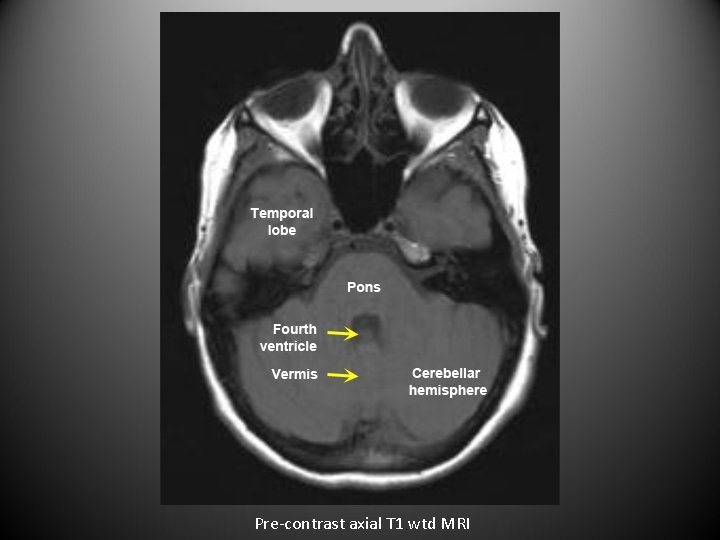

• For axial images you need to know the level. • The next set of images are axial sections of brain from top to bottom.

Pre-contrast axial T 1 wtd MRI